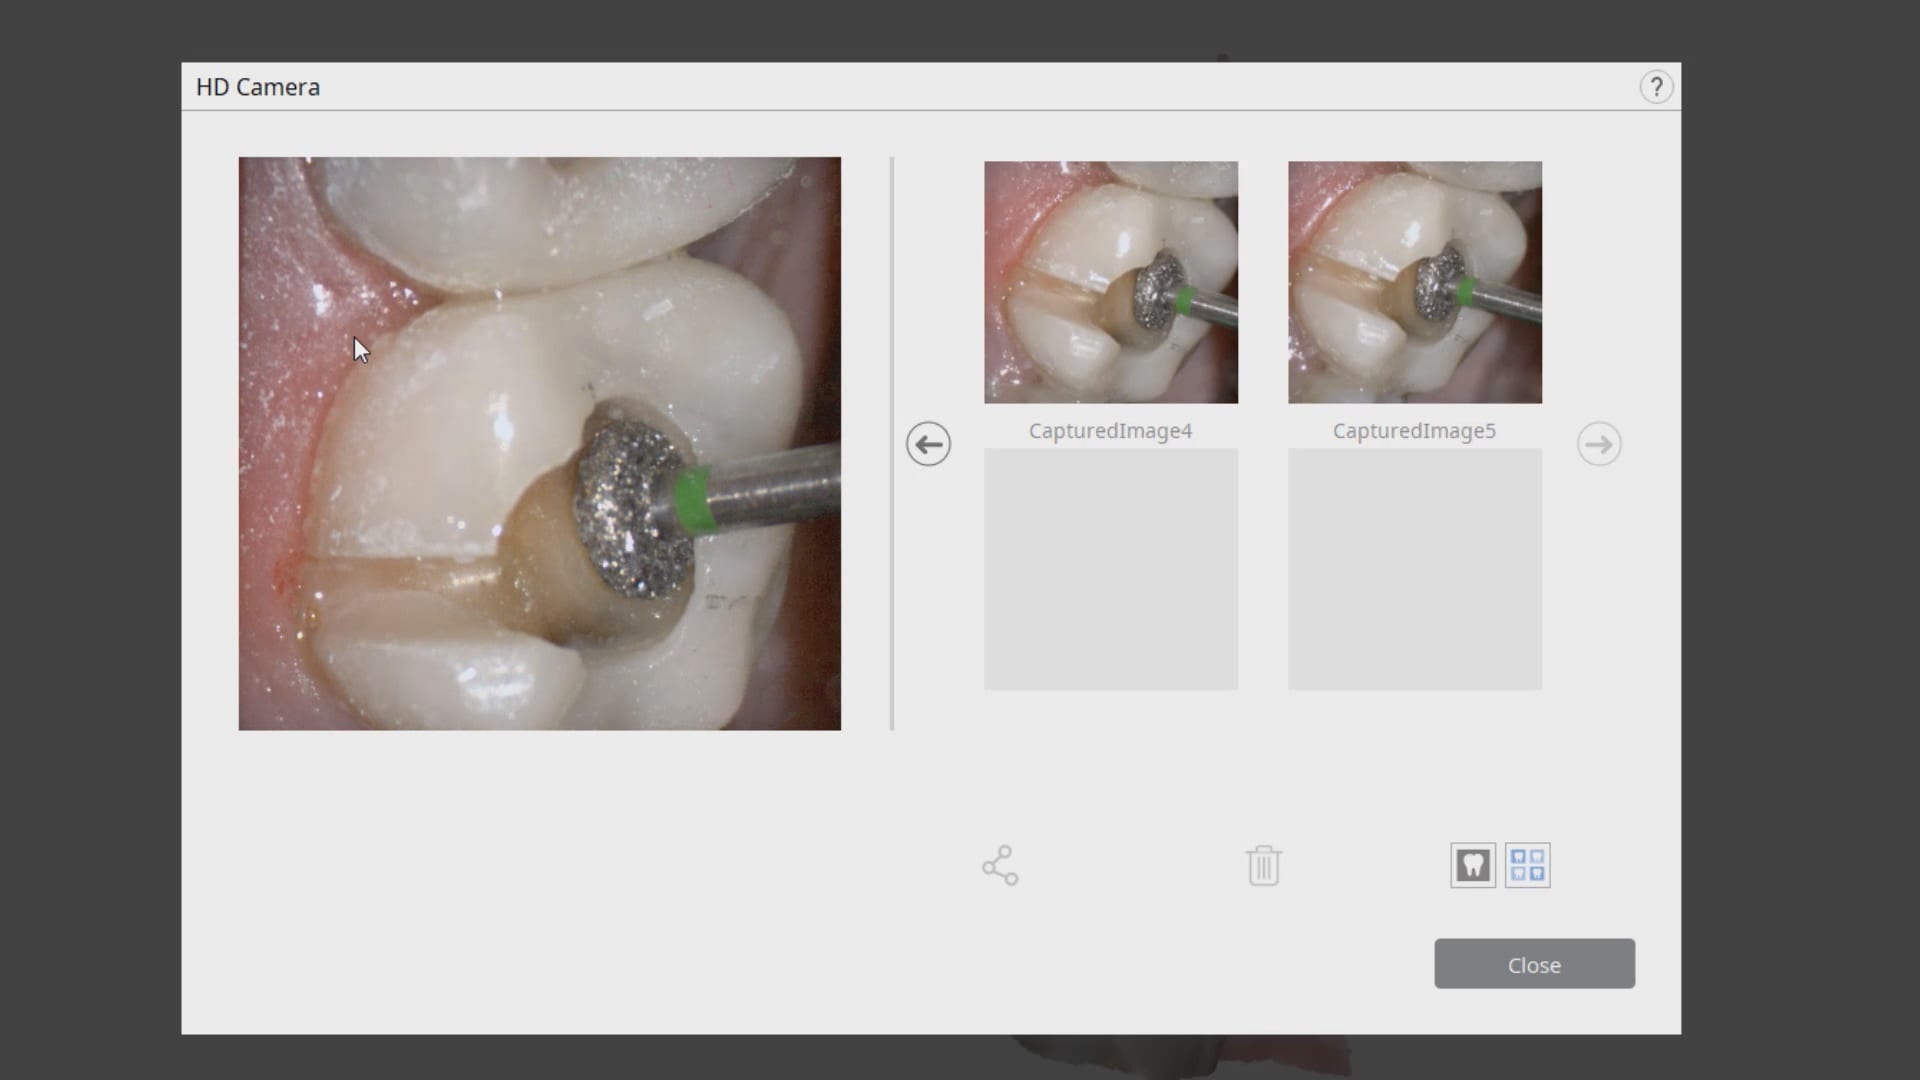

September 3, 2019In this case presentation, we feature a crown that needs to be replaced due to open margins and recurrent decay. With the Medit i500, after the patient is anesthetized and […]

In this case presentation, we feature a crown that needs to be replaced due to open margins and recurrent decay. With the Medit i500, after the patient is anesthetized and […]